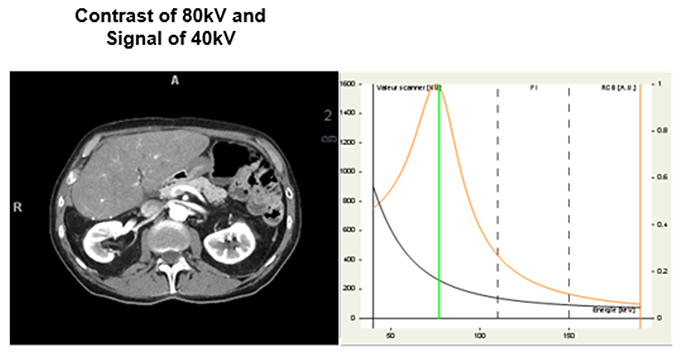

The integrated concept with the introduction of dual-energy acquisition.

It’s the contrast/noise ratio in the image with iodine contrast injection. In general, the best value is obtained for the image energy of 70KeV.

Let’s look at the differences in these four images taken at different dual energy levels. Compare the streak artifacts with the 80kV, 140 kV, the mixed acquisition of 140kV and 80 kV and the last at 140 keV.